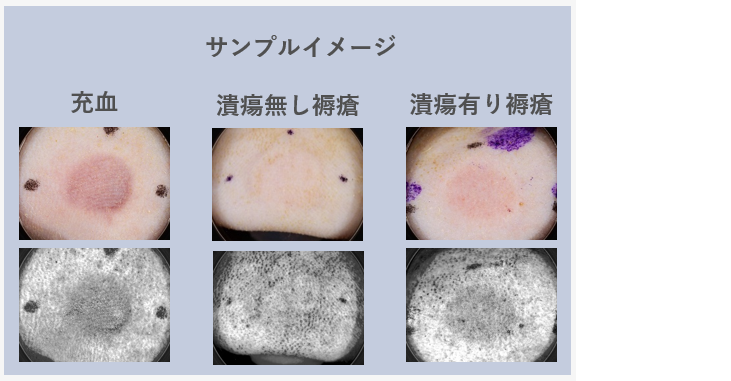

褥瘡エコーの個人的マニュアル - 南砺の病院家庭医が勉強記録を始めました。An archive of medical articlessummarized by a family physician from Nanto Municipal Hospital。

はじめての褥瘡エコー 前編 かんかん! -看護師のためのwebマガジン by 医学書院。

褥瘡エコーの個人的マニュアル - 南砺の病院家庭医が勉強記録を始めました。An archive of medical articlessummarized by a family physician from Nanto Municipal Hospital。

AIで褥瘡を早期発見! 長野県看護大学×マクニカ共同プロジェクト 前編- AI事業 - マクニカ。

はじめての褥瘡エコー 前編 かんかん! -看護師のためのwebマガジン by 医学書院。

はじめての褥瘡エコー 前編 かんかん! -看護師のためのwebマガジン by 医学書院。

はじめての褥瘡エコー 前編 かんかん! -看護師のためのwebマガジン by 医学書院。